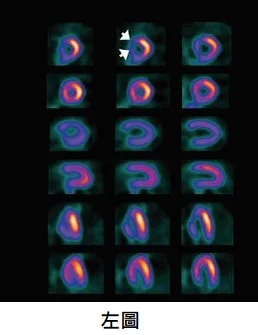

【113-2 醫學(三) 第14題】有關心臟核子醫學心肌灌注掃描SPECT的描述,何者錯誤?

這題的核心在於理解心肌灌注掃描(SPECT)的影像判讀原則,以及它與電腦斷層冠狀動脈造影(CCTA)在診斷冠狀動脈疾病(CAD)上的優劣比較。圖片中左圖顯示的是可逆性灌注缺損,右圖是固定性灌注缺損。